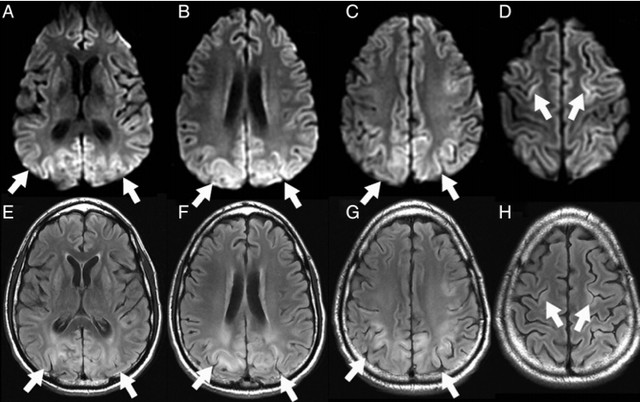

癫痫介导的脑部影像改变 对于有明确癫痫发作病史的患者,癫痫介导的脑部影像学改变需要考虑,不同于癫痫的病因(肿瘤、FCD 等),癫痫介导的脑部影像学改变往往是可逆的,磁共振上大多表现为 T2WI 高信号,约半数表现为 DWI 高信号,常见的受累部位包括皮层 / 皮层下、基底节区、白质、胼胝体、小脑,而临床上无其他特异性的表现,如图 2 所示。

图 2 42 岁女性,延长的亚临床癫痫持续状态患者所做的两次头颅 MR 结果。A 为 T2WI,B、C、F 为 DWI,D 为 ADC 图,E、G 为 FLAIR,可见发病 4 天时双侧顶枕叶可见明显 DWI 高信号病灶,T2 相也为高信号,ADC 低信号,发病 25 天时,病灶消失